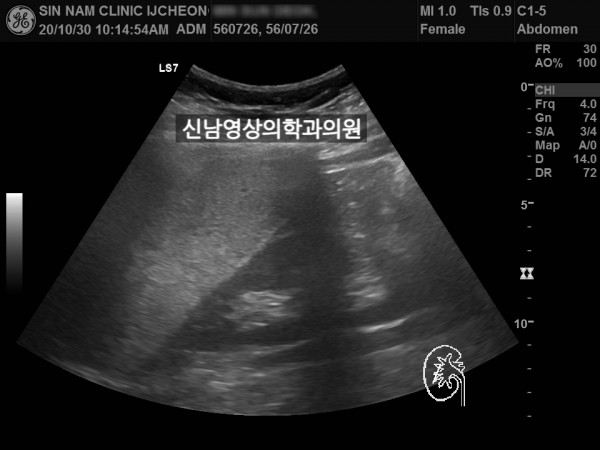

좌측 신장 지방혈관종 추적검사中 우측 신장의 종괴를 발견했습니다.

차후 신장암으로 수술하셨습니다.

초음파 당시 증세는 없었습니다.